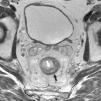

Grado de infiltración del tumorEn el diagnóstico por RM, cualquiera de las capas de la pared rectal se considera infiltrada en cualquier punto de su extensión cuando su intensidad de señal propia queda sustituida por la de la masa tumoral. Se describen varios estadios de infiltración según esta afecte a las diferentes capas del recto, mesorrecto u otras estructuras pélvicas. Un estadio T1 (fig. 2) implica la afectación de la mucosa y submucosa pero no así de la muscular, de manera que se conserva la hipointensidad de esta capa a lo largo de todo el anillo rectal, quedando la extensión del tumor por ella misma delimitada, sin ser invadida. Un estadio T2 (fig. 3) supone la afectación de la capa muscular, caso en el que su hipointensidad se pierde y se sustituye por la intensidad de señal del tumor, aunque conserva su contorno, sin infiltración en la grasa mesorrectal. Un estadio T3 (fig. 4) implica infiltración más allá de la muscular, por lo que el tumor se aprecia en la grasa como un frente redondeado o nodular3. La presencia de espiculaciones no es evidencia suficiente de infiltración3,4, ya que pueden estar causadas por fibrosis o por una inflamación peritumoral. Un estadio T4 (fig. 5) se da cuando la infiltración es de gran alcance y, rebasando la fascia mesorrectal, afecta a otras estructuras pélvicas, la hoja peritoneal (estadio T4a) o, una vez perforada esta, las vísceras intraperitoneales (estadio T4b).